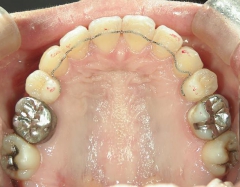

矯正歯科 治療前